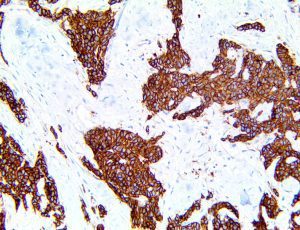

The first cytokines released are interleukin 1β (IL-1β) and tumor necrosis factor-α (TNF-α), which attract a variety of circulating white blood cells (WBCs) to the infection site, including neutrophils, monocytes, macrophages, and natural killer (NK) cells. This response, along with the antipathogenic chemicals released by these cells (i.e., complement), comprise the innate immune response. These cells directly attack the invading pathogen and also release additional cytokines, chief among them interleukin-1 and 6 (IL-6). IL-6 is essential for invoking the adaptive immune response, which calls T-cells, B-cells, and T helper (Th) cells to the infection site. IL-6 also stimulates further recruitment, proliferation and activation of macrophages.

It is the ICU physician who is most likely to witness one of the deadliest manifestations of the abnormal immunological response, the cytokine storm syndrome (CSS). This response is also referred to by some as the cytokine release syndrome (CRS). CSS is characterized by continuous activation and expansion of macrophage and lymphocyte populations, which secrete large amounts of cytokines, causing the cytokine storm. This massive cytokine release is akin to hemophagocytic lymphohistiocytosis (HLH) disease, a syndrome characterized by initial unchecked and persistent activation of cytotoxic T lymphocytes and NK cells.

This activation induces inflammatory monocytes to highly express IL-6, starting a localized and then systemic cascade effect that results in hyperproduction of IL-6, which accelerates the inflammatory process. Because IL-6 also increases vascular permeability, excessive levels cause blood vessels to become very leaky. This, along with clotting factors released from vascular endothelial cells, stimulates the coagulation cascade, resulting in microthrombosis (tiny clots), which leads to ischemia and tissue death of the kidney, intestines, heart, liver, brain and extremities.